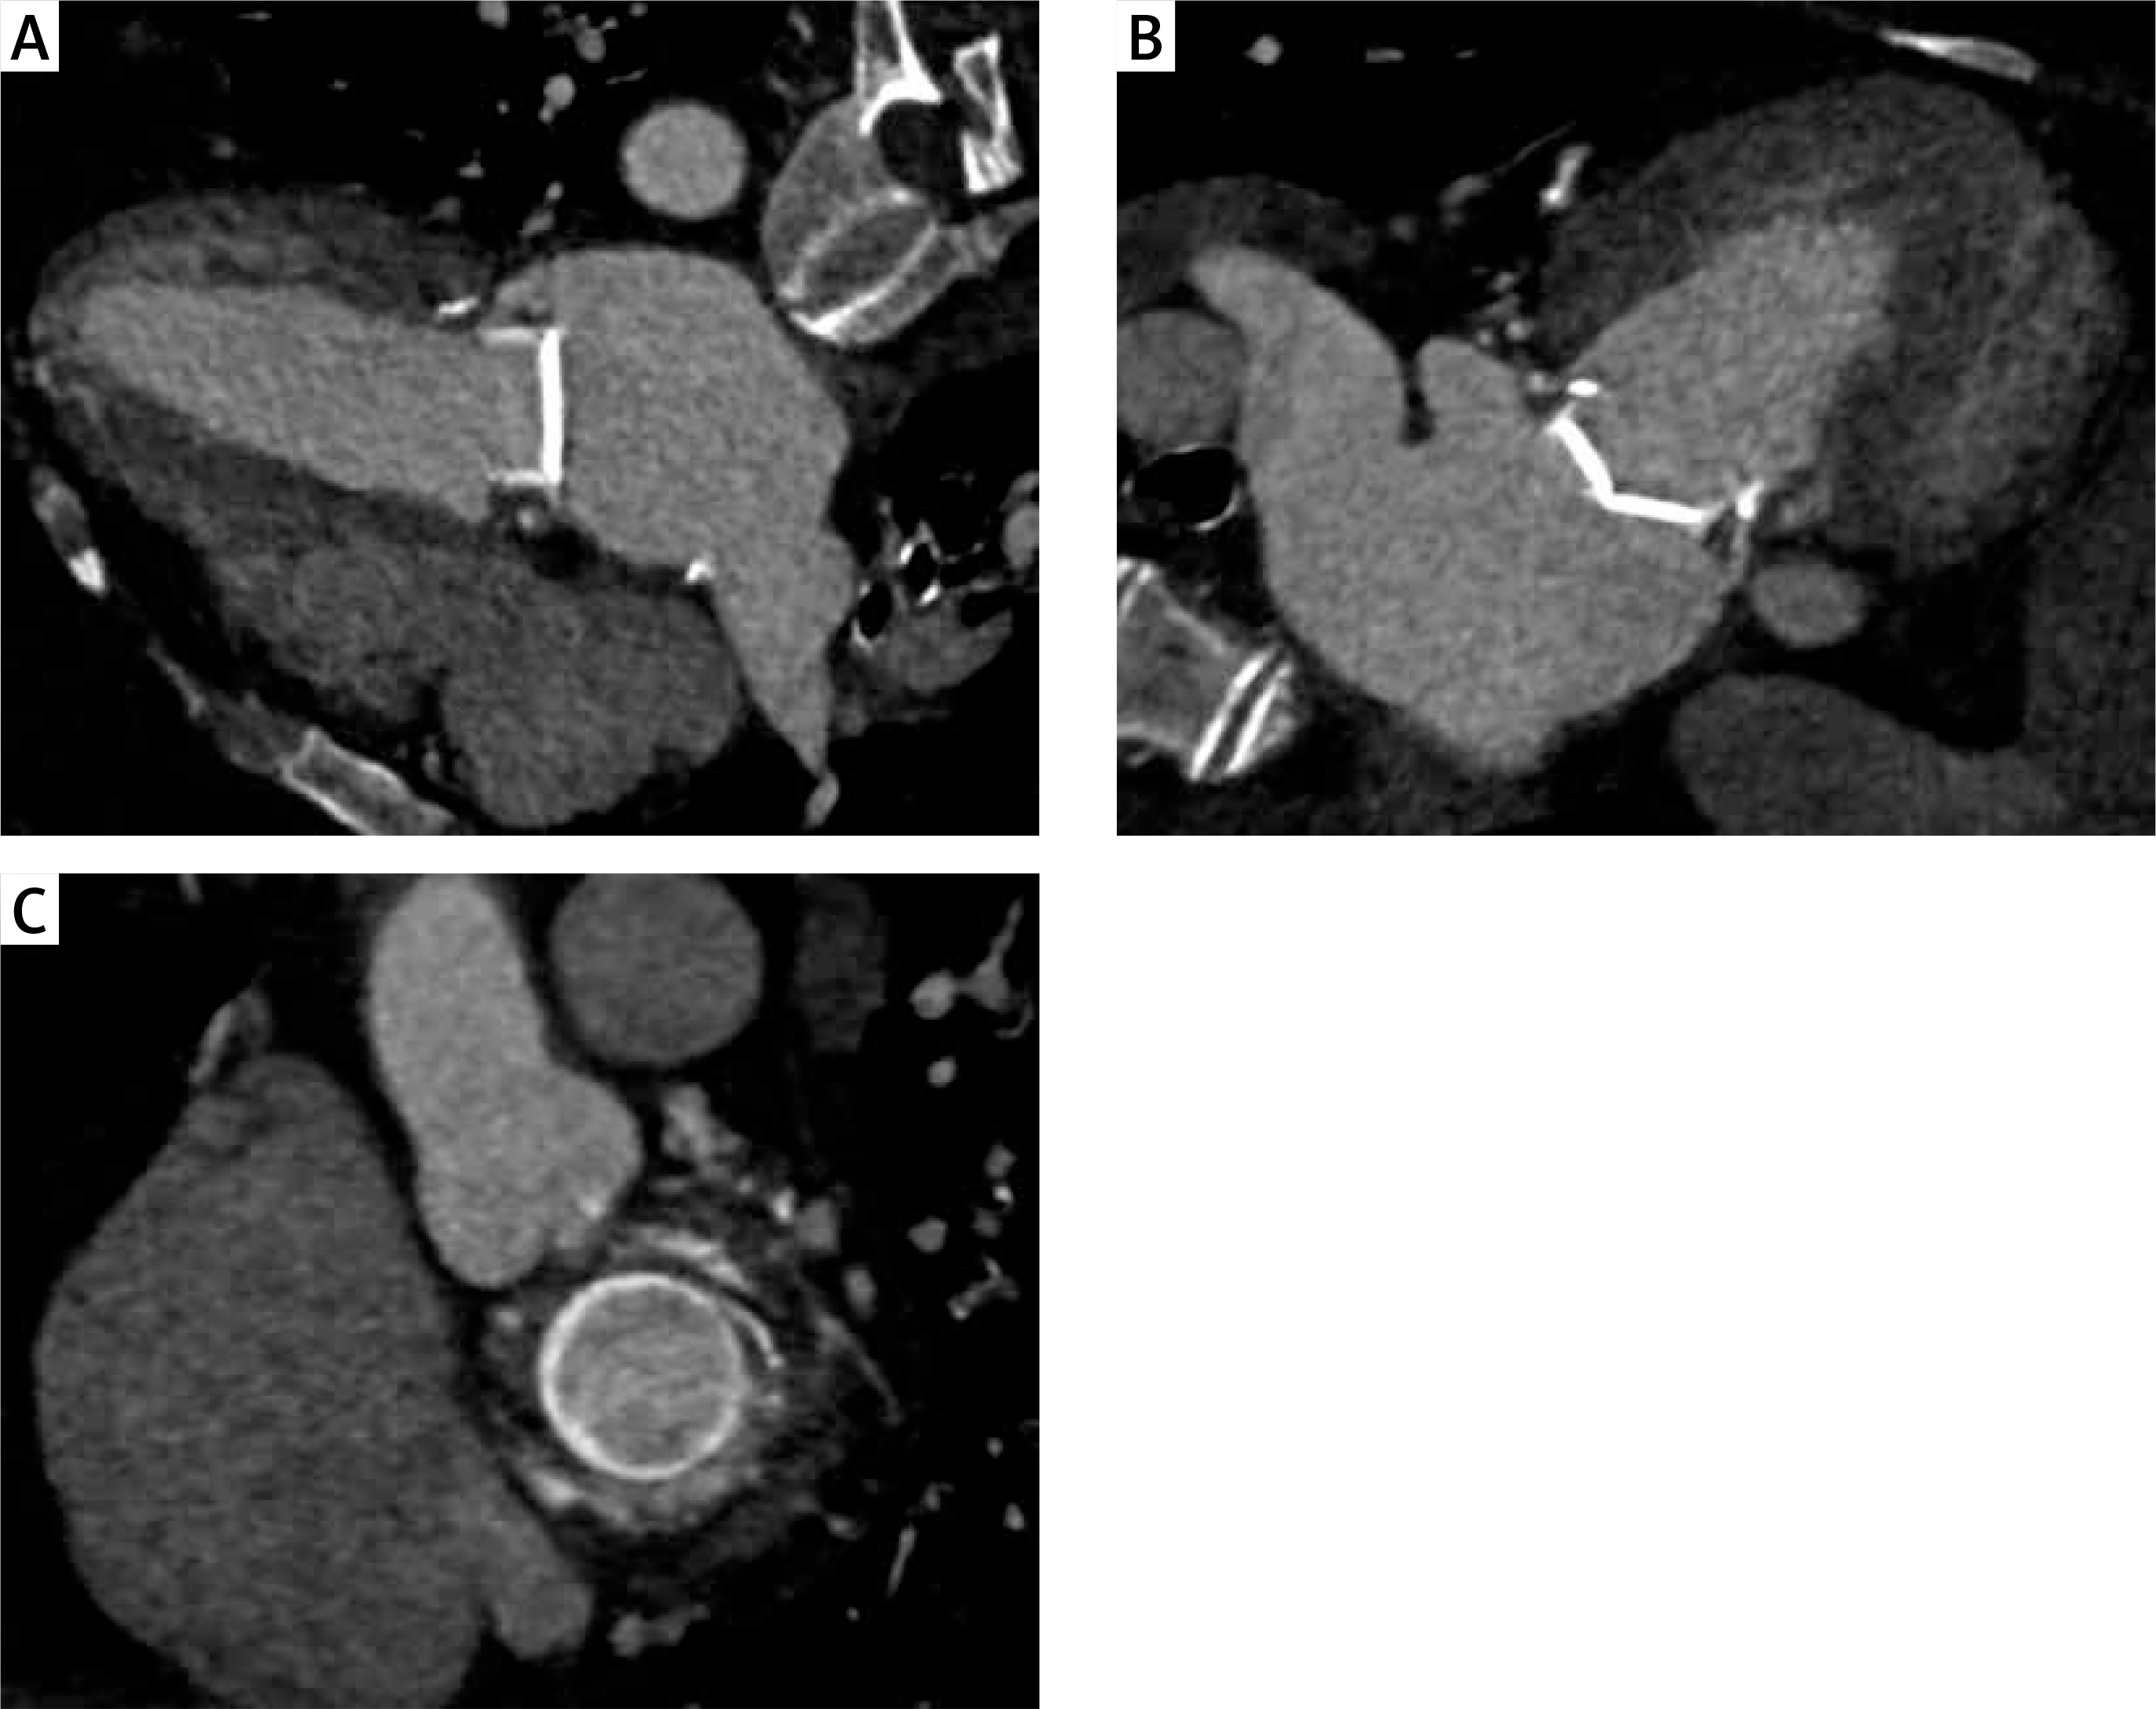

Figure 1

Paravalvular leak assessment using CT scan. A, B – 2-chambers views. The CT image at the level of the mitral annulus shows a small defect at the periphery of the prosthetic valve. The defect is continuous with the lumen of the LVOT and ascending aorta. C – Short axis view from the atrium. This view confirms the location of the mild posterolateral defect and shows surrounding structures